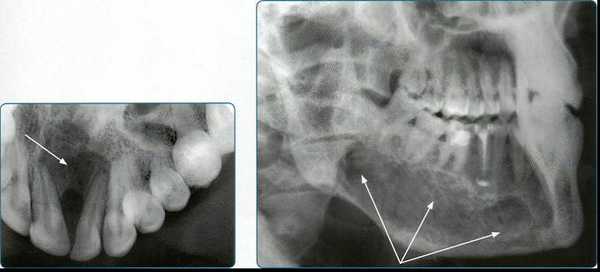

Прямые панорамные рентгенограммы имеют преимущество перед внутриротовыми снимками по богатству деталями изображения костной ткани и твердых тканей зубов. При минимальной лучевой нагрузке они позволяют получить широкий обзор альвеолярного отростка и зубного ряда, облегчают работу рентгенолаборанта и резко сокращают время исследования. На этих снимках хорошо видны полости зуба, корневые каналы, периодонтальные щели, межальвеолярные гребни и костная структура не только альвеолярных отростков, но и тел челюстей. На панорамных рентгенограммах выявляются альвеолярная бухта и нижняя стенка верхнечелюстной пазухи, нижнечелюстной канал и основание нижнечелюстной кости.

На основании панорамных снимков диагностируют кариес и его осложнения, кисты разных типов, новообразования, повреждения челюстных костей и зубов, воспалительные и системные поражения. У детей хорошо определяется состояние и положение зачатков зубов.

Ортопантомограммы демонстрируют взаимоотношения зубов верхнего ряда с дном верхнечелюстных пазух и позволяют выявить в нижних отделах пазух патологические изменения одонтогенного генеза.

Особенно важно использовать ортопантомографию в детской стоматологии, где она не имеет конкурентов в связи с низкими дозами облучения и большим объемом получаемой информации. В детской практике ортопантомография помогает диагностировать переломы, опухоли, остеомиелит, кариес, периодонтиты, кисты, определять особенности прорезывания зубов и положение зачатков.